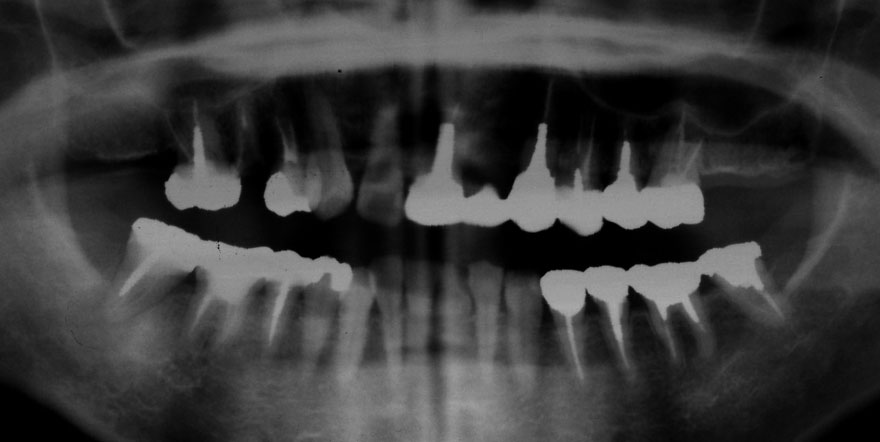

初診時 16歳 女性

若年性歯周疾患

27年後 43歳

初診時 18歳 女性 平均歯槽骨喪失量:0.87mm

平均歯槽骨喪失量:1.40mm

28年間喪失量:-0.52mm

年間喪失速度:-0.02mm

(ケア頻度:5.96ヵ月ごと)